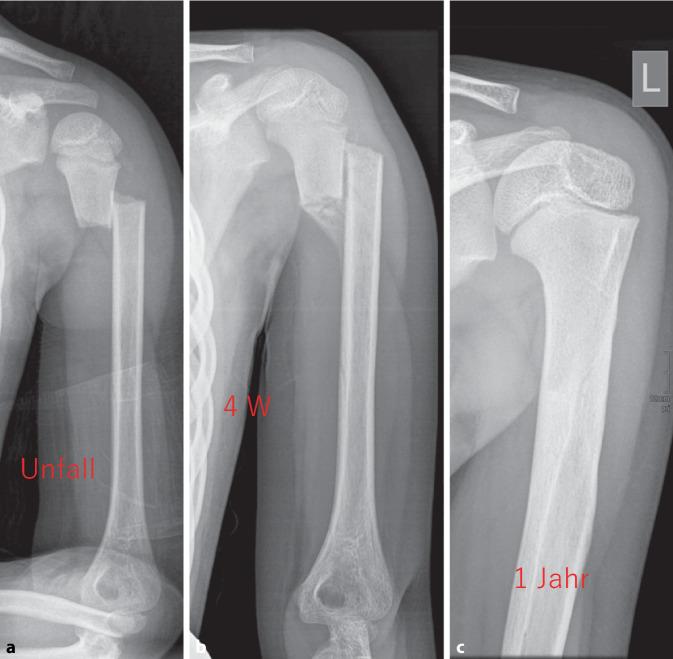

The measurement of axial deviation and tilt is not interobserver and intraobserver reliable [3]. The age limit for when complete correction is possible was set at an age of 10 years, as the correction potential changes around this age. For diagnostic purposes, well-centered X‑ray images in 2 planes (true AP and Y‑images without thoracic parts) is defined as the standard. At the age of less than 10 years, any malposition can be treated conservatively with Gilchrist bandaging for 2-3 weeks. Surgery can only be indicated in individual cases, e.g., in the event of severe pain or the need for rapid weight bearing. An ad latus displacement of more than half the shaft width should not be tolerated over the age of 10 years. Due to the variance in the measurement results, it is not possible to recommend surgical treatment depending on the extent of the ad axim dislocation. As a guideline, the greater the dislocation and the closer the child is to growth joint closure, the more likely surgical treatment is indicated. The development should be taken into account. The gold standard is retrograde, radial and unilateral ESIN osteosynthesis using two intramedullary nails. Osteosynthesis does not require immobilization. A follow-up X‑ray is planned for unstable fractures without osteosynthesis after 1 week, otherwise optional for documentation of consolidation after 4-6 weeks, e.g., if sports clearance is to be granted and before metal removal (12 weeks).

Recommendations for surgical indications based on the extent of tilt are not reproducible and seem difficult in view of the current literature [3, 9, 12]. A pragmatic approach is recommended. The prognosis of the fracture appears to be so good, taking the algorithm into account, that restitutio ad integrum can be expected in most cases.